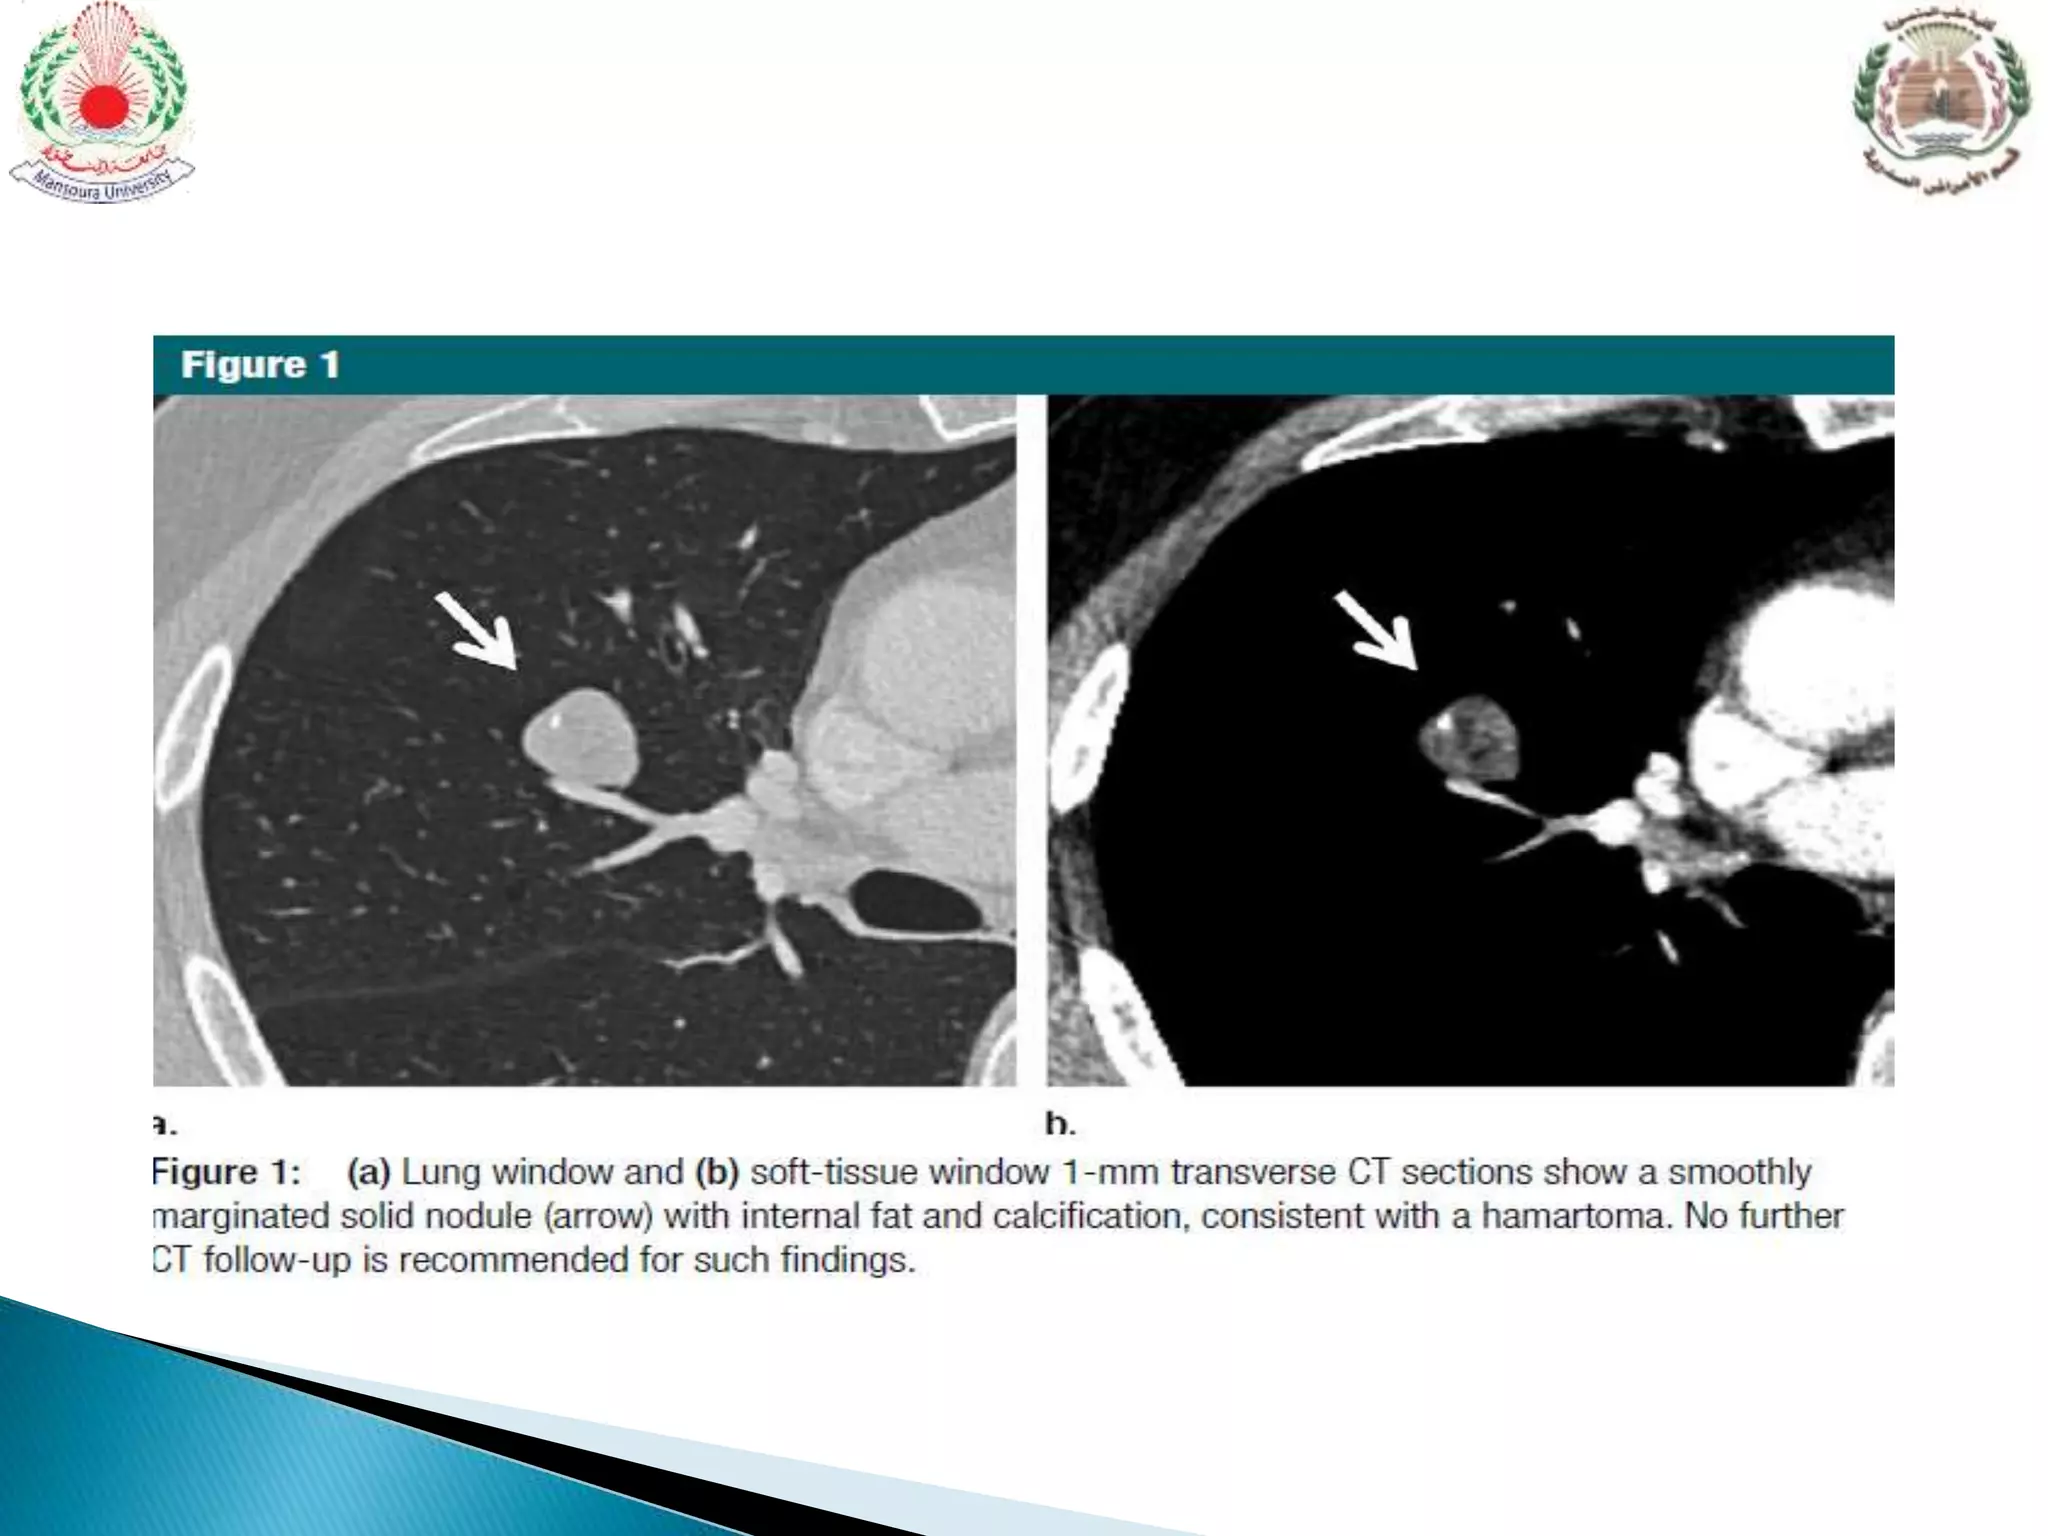

 Hamartoma